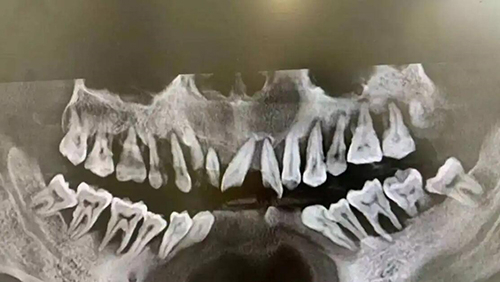

根管治疗是一种用于治疗牙齿神经及周围组织疾病的方法,通常是因为牙髓受损或感染导致牙齿疼痛或其他症状。

在根管治疗完成后,牙齿可能会变得脆弱,容易受到损坏。

首先,根管治疗后的牙齿可能会变得脆弱,容易发生断裂或破损。